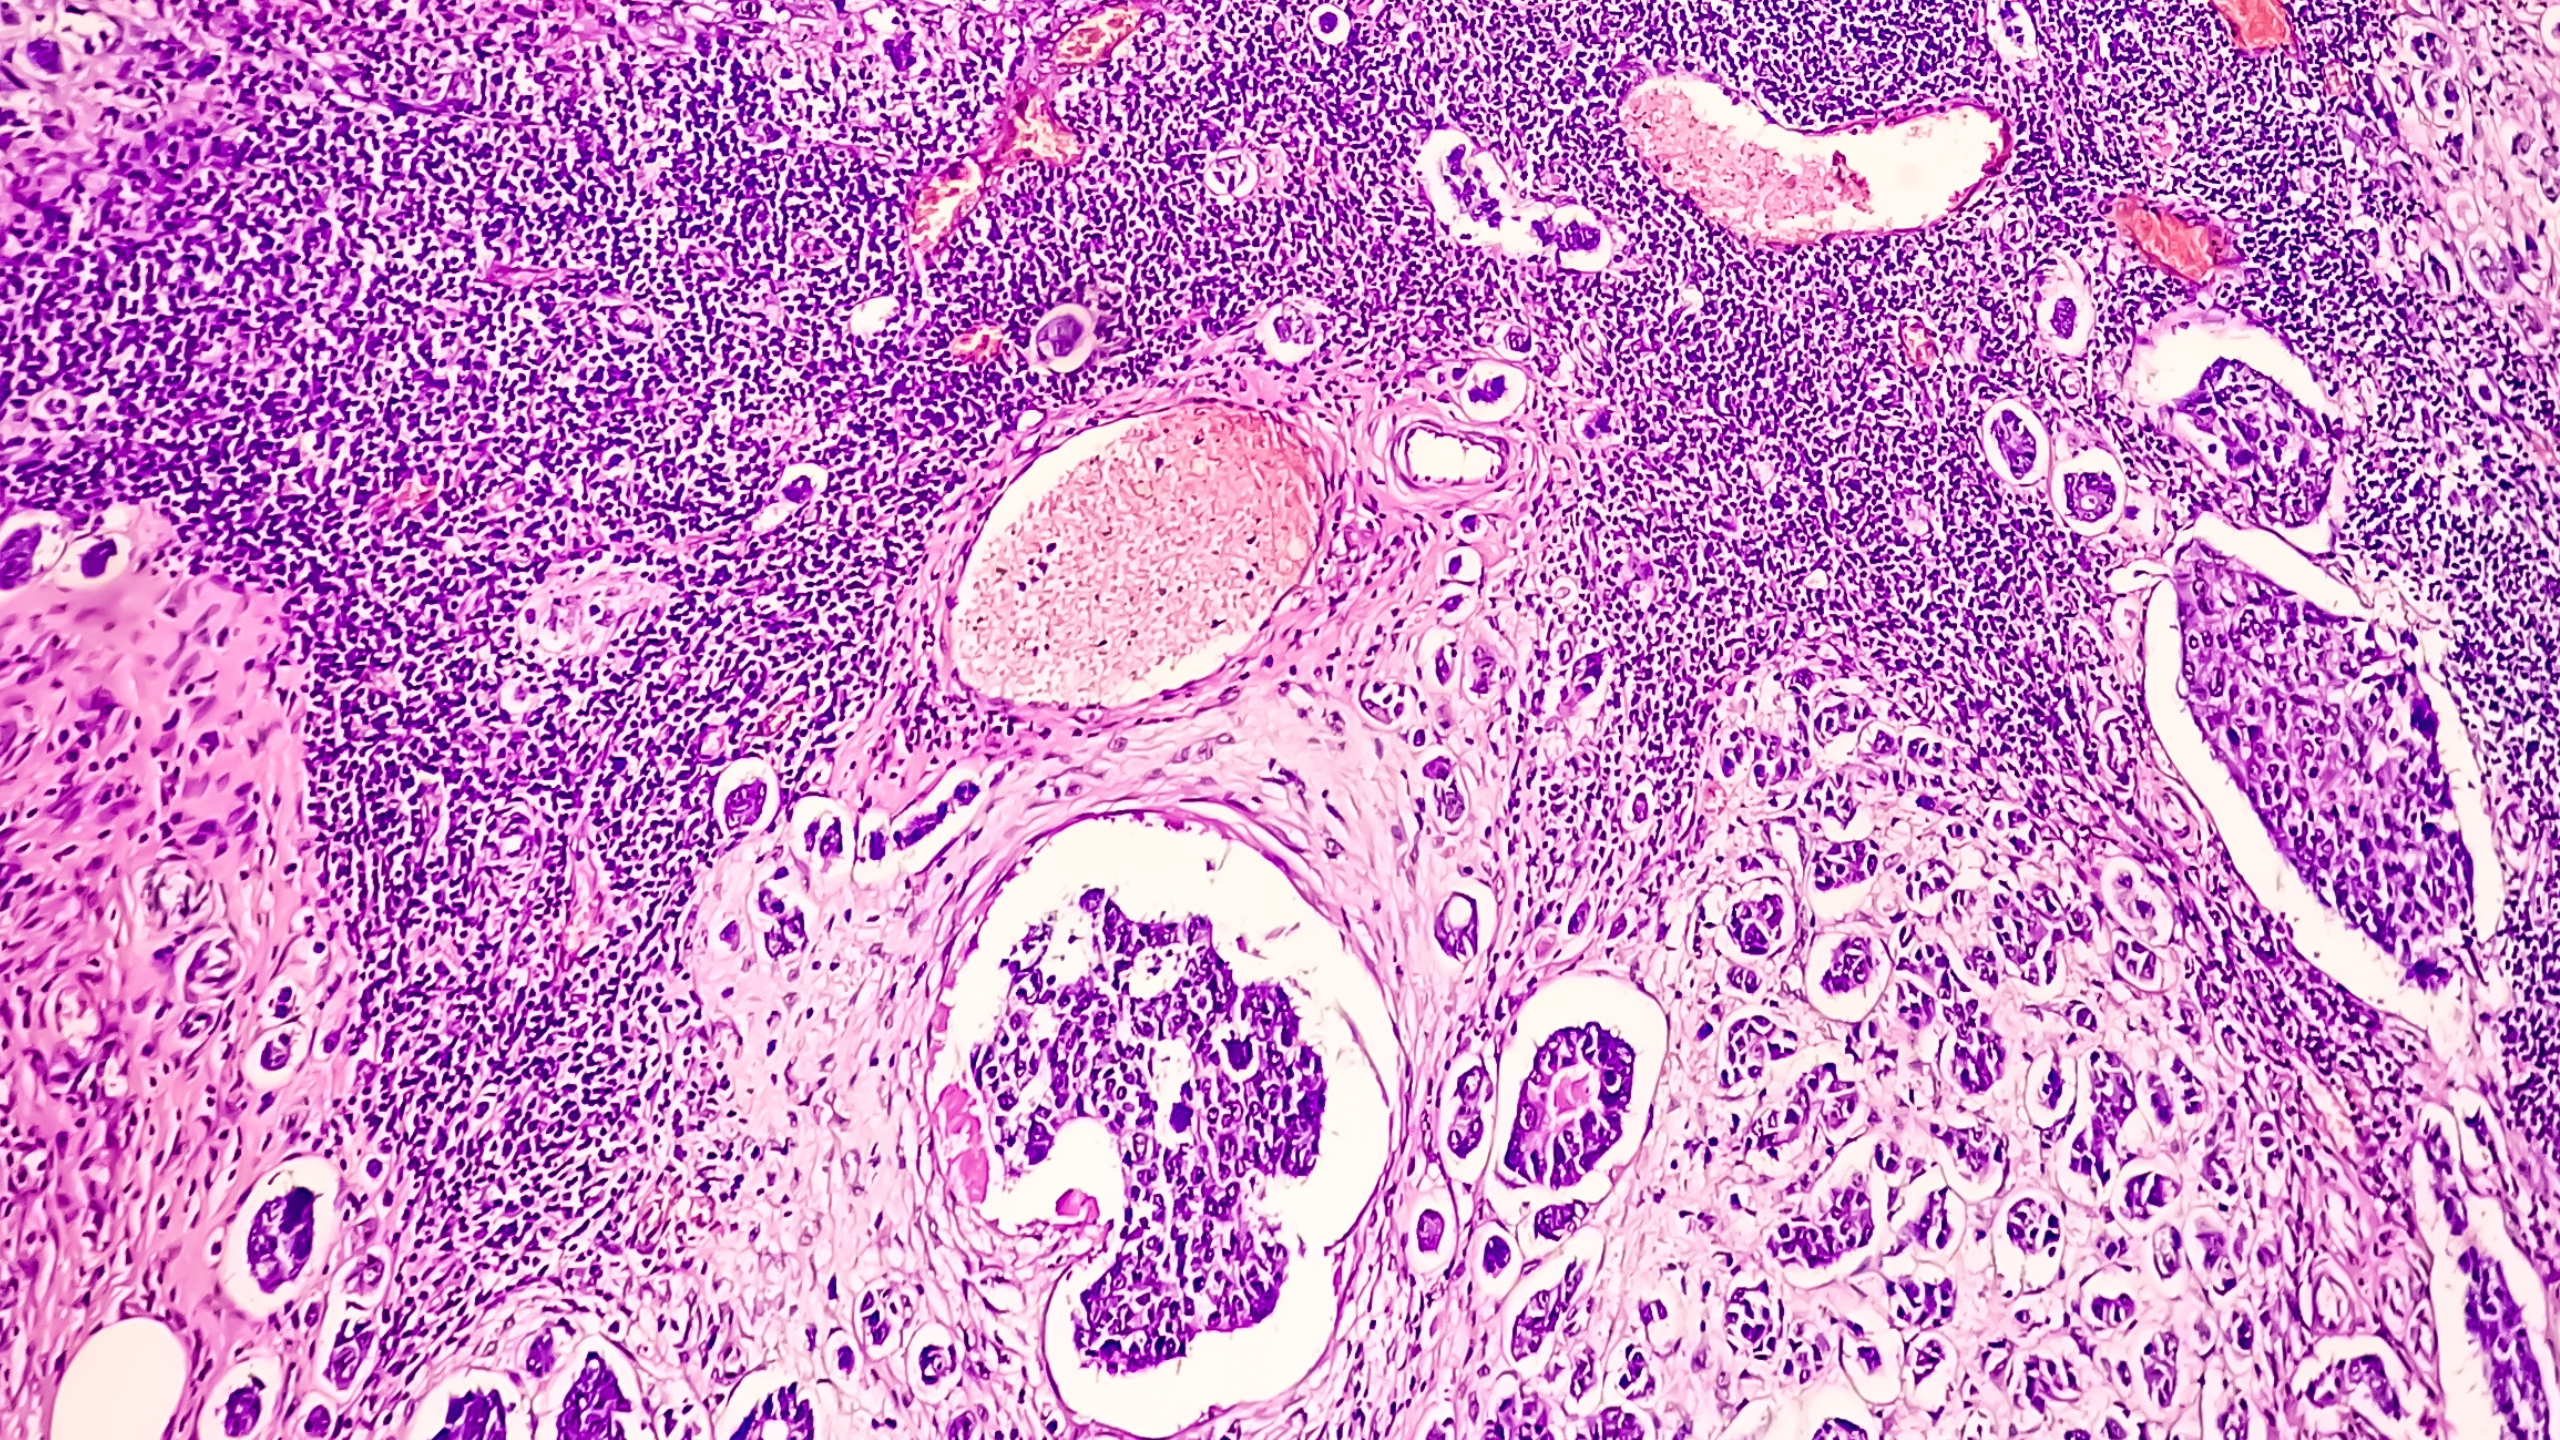

Some cancer cells are coated with proteins that allow them to hide from immune cells and continue to grow. In a research collaboration with Pfizer Inc. two such proteins, CD47 and PD-L1, were ‘unmasked’, exposing the cancer cells to the immune system for destruction.

While therapies targeting CD47 and PD-L1 have been tested individually, they both present limitations such as toxicity to patients or poor response rates. Therefore, dual-target antibody therapy that can maximise their anti-cancer functions while minimising these obstacles was explored.